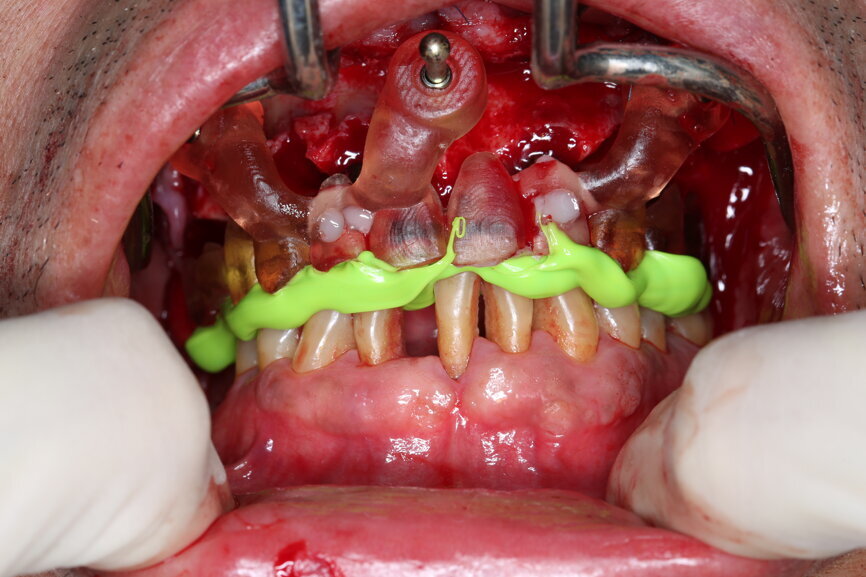

On the day of surgery, we prepared for the surgical protocol provided by the implant planning software, which guided us on the drilling sequence and the use of the appropriate instruments for the implant bed preparation (Figs. 30a & b). After the fixation pins had been allocated, teeth #17, 16, 15, 13, 12, 22, 23 and 24 were atraumatically extracted and alveolectomy was performed using a bone reduction guide (Figs. 31–36). Four implants (Straumann BLX; regular base; diameter: 4.5 mm; length: 12.0 mm) were placed, two straight implants in the anterior and two titled implants in the posterior. All the implants were stabilised to a torque of 50 Ncm (Figs. 37–43), and the SRAs were placed on top. The SRAs on the posterior implants had an angulation of 30° (diameter: 4.6 mm; gingival height: 3.5 mm) and on the anterior implants an angulation of 17° (diameter: 4.6 mm; gingival height: 3.5 mm; Figs. 44 & 45).

The bite registration guide was fixed with pins, and the open-tray impression copings were placed on the SRAs of the anterior implants, which were fixed with the guide using flowable composite and then sent to the laboratory (Figs. 46–50). Afterwards, we checked the CAD/CAM temporary restoration which had been designed and milled before surgery (Fig. 51), and protective caps were placed on the SRAs, followed by bone grafting using cerabone granules (botiss biomaterials) with a 1–2 mm grain size in the extraction sockets and suturing (Figs. 52–54).